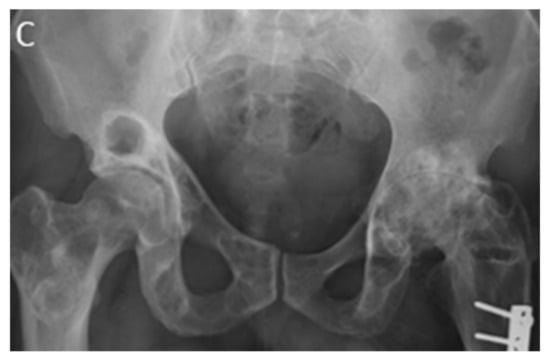

Fibrous dysplasia presents as a well-defined intramedullary osteolytic lesion with fusiform bony expansion and endosteal scalloping with preservation of cortical contour (Figure 8a). Increased trabeculation, thickened cortex, and “Ground glass” appearance caused by amorphous woven bone formation are other imaging findings (Figure 8c). FD has typical low intensity on T1-weighted and variable low to high intensity on T2-weighted MRI sequences depending on varying amounts of fibrous tissue (Figure 8b) [16,28]. FD metabolic activity on 18F-FDG PET/CT ranges from normal to intense, and it depends on the number of proliferating fibroblasts [29].

Figure 8.

A 24-year-old man with multiple bone lesions. (A) The axial non-contrast CT in bone window demonstrates expansile lytic bone lesion with intact cortex within the spinous process of thoracic vertebrae (arrow); no periosteal reaction, cortical disruption, or soft tissue mass was found. (B) Sagittal T1W image shows expansile bone lesions with hyposignal intensity and intact cortex within the spinous process of multiple cervical spines (arrow). (C) Frontal image of pelvis shows bilateral expansile lytic bone lesions with bubbly appearance and typical shepherd’s crook deformity in the left side.